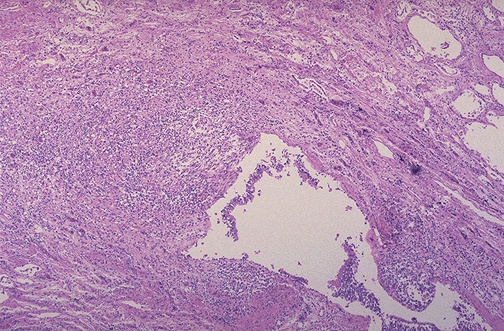

| The mid lower portion of this photomicrograph demonstrates a dilated bronchus in which the mucosa and wall is not clearly seen because of the necrotizing inflammation with destruction. This is the microscopic appearance of bronchiectasis. Bronchiectasis is not a specific disease, but a consequence of another disease process that destroys airways. |